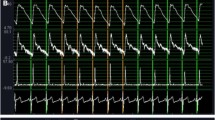

Wave intensity analysis. Artwork by Piet Michiels, Leuven, Belgium

Wave intensity analysis. Artwork by Piet Michiels, Leuven, Belgium

WI has another important feature . During the period of the first positive peak, which appears in early ejection (Fig. 11.1), P b and U b are practically zero, and hence WI b is also practically zero. Thus, we have

where P is actually measured pressure. Let W1 be the height of the first peak (Fig. 11.1); then we have

When peak dP/dt is measured in the ascending aorta, aortic peak dP/dt is approximately equal to LV peak dP/dt unless there is aortic stenosis. The strong correlation between W1 in the aorta and LV peak dP/dt (r = 0.84, P < 0.0001) was confirmed by animal experiments [11].

Noninvasive Measurements of Wave Intensity

In our method of obtaining carotid arterial WI [12], the carotid diameter-change waveform was used as a surrogate for the carotid-pressure waveform. The blood-flow velocity averaged along the Doppler beam (Fig. 11.2, line B) crossing the carotid artery was measured using range-gated color-Doppler signals. Because the carotid artery is apart from the ascending aorta, carotid arterial W1 may not represent LV peak dP/dt. Nevertheless, the correlation between carotid arterial W1 and LV peak dP/dt was confirmed by clinical measurements (Fig. 11.3) [13]. The FFR was obtained as the linear regression line of W1 on HR. Then we analyzed the differences in the slope of W1–HR relations.